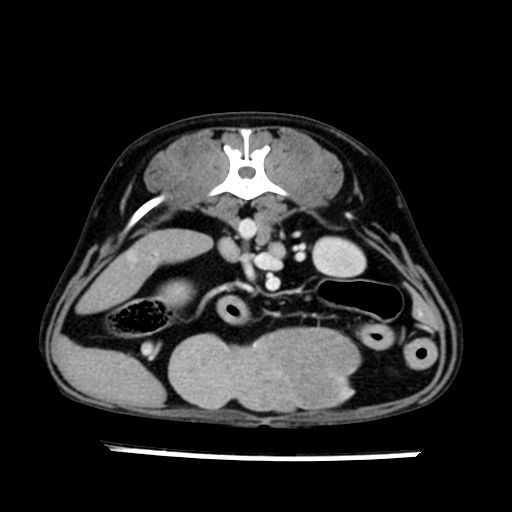

prescritto esame TAC

sequenza immagini limitata al fegato reni e surreni

le immagini ecografiche rispetto alla tac datano circa 7 mesi prima ,le surrenali sono normali nonostante il test acth sia risultato positivo .all’esame TAC dopo diversi mesi risultano aumentate armonicamente nel volume e si individua un forte sospetto di adenoma ipofisario .

sospetto adenoma ipofisario vs. meno probabilmente meningioma della base; intertiziopatia polmonare; lesione espansiva epatica, verosimilmente del lobo laterale sinistro, di sospetta natura neoplastica; lesioni spleniche di natura da definire; iperplasia/ipertrofia delle ghiandole surrenali, bilateralmente; vertebra di transizione del rachide toracico; tenosinovite cronica del muscolo bicipite brachiale di destra.